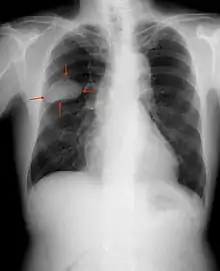

Small cell lung cancer

When associated with the lung, it is sometimes called "oat cell carcinoma" due to the flat cell shape and scanty cytoplasm. Caution is required when diagnosing SCLC, because small cell mesothelioma – an extremely rare subtype of lung cancer – can be mistaken for small cell lung cancer.[16]

Small-cell carcinoma is most often more rapidly and widely metastatic than non-small-cell lung carcinoma[19] (and hence staged differently). There is usually early involvement of the hilar and mediastinal lymph nodes. [18] The mechanisms of its metastatic progression are not well-understood.[20]